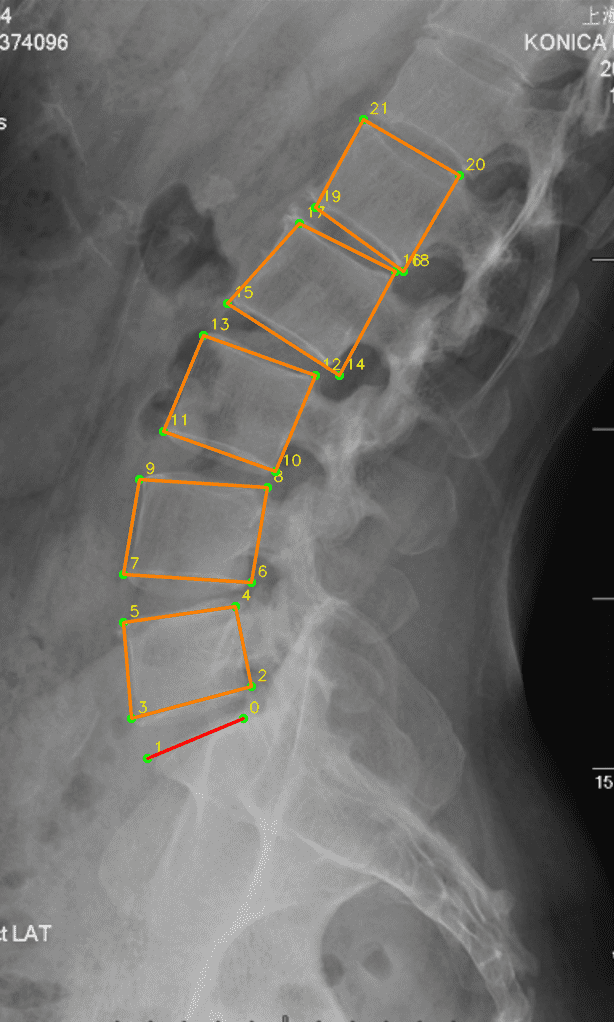

1. L4/L5 Locator (X-Ray)

约 4000 例 Sagittal X-Ray 图片训练,使用 HRNet ,输出线性标记直接分类预测椎点。

- 骨架:采用 HRNet (High-Resolution Network) 作为主干,保持多尺度并行高分辨率流并在阶段间反复交换信息,提升对位置敏感任务(关键点定位、线段化)的空间精度。参考:Wang et al., arXiv:1908.07919。

将传统通过点标记训练的 UNet 峰值 22 通道分类模型 + UNet ROI 窗口粗分割模型 替换为对线性顺序和先验顺序更精确的 HRNet 模型,识别率提高并且对于复杂情况的识别能力大幅提升。

椎骨 / 髂骨 精确标记例